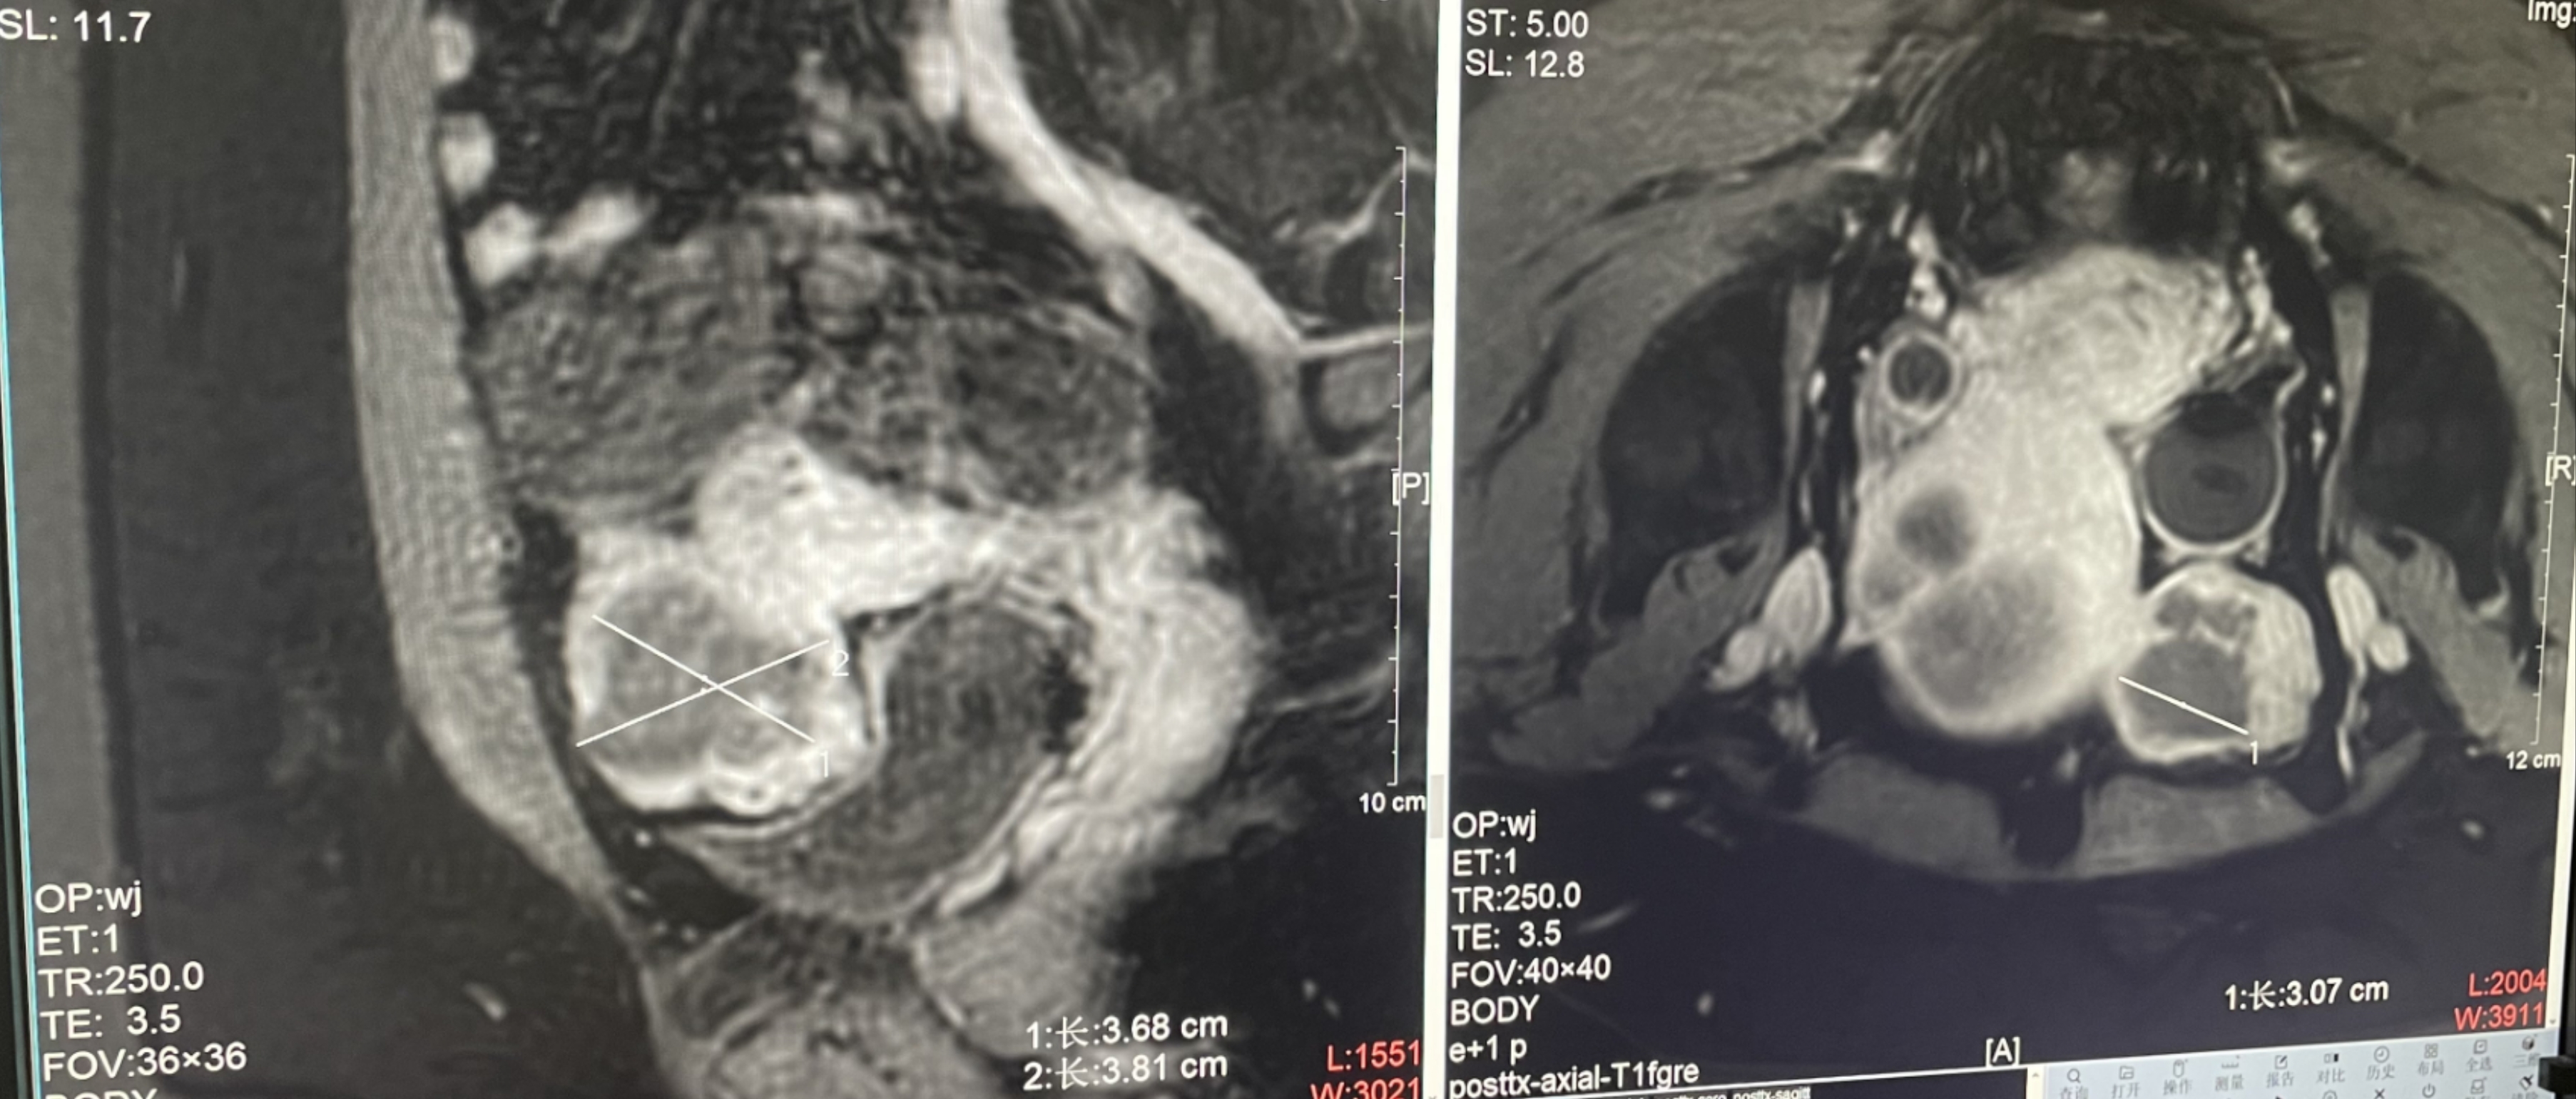

Uterine fibroids

Patient Information:Female,38

Diagnosis: Uterine fibroids

Tumor size: about 38*40*42mm

Postoperative evaluation: Postoperative enhanced imaging showed a good overlap between the ablation area (right) and the tumor area (left), the non-perfusion area was continuous and consistent.

Conclusion:It has a excellent ablation effect on this tumor, and the temperature rise curve during treatment is in line with expectations. The 240CEM area of each treated target is large, full and continuous.The ablation effect was very good,the NPV volume ratio was about 87.88%.